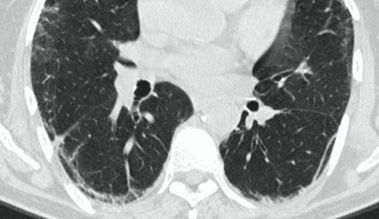

4.3. ЛУЧЕВАЯ ДИАГНОСТИКА COVID-19

Методы лучевой диагностики применяют для выявления COVID-19 пневмоний, их осложнений, дифференциальной диагностики с другими заболеваниями легких, а также для определения степени выраженности и динамики изменений, оценки эффективности проводимой терапии.

К методам лучевой диагностики патологии ОГК пациентов с предполагаемой/установленной COVID-19 пневмонией относят:

- Обзорную рентгенографию легких (РГ),

- Компьютерную томографию легких (КТ),

- Ультразвуковое исследование легких и плевральных полостей (УЗИ).

Стандартная РГ имеет низкую чувствительность в выявлении начальных изменений в первые дни заболевания и не может применяться для ранней диагностики. Информативность РГ повышается с увеличением длительности течения пневмонии. Рентгенография с использованием передвижных (палатных) аппаратов является основным методом лучевой диагностики патологии ОГК в отделениях реанимации и интенсивной терапии (ОРИТ). Применение передвижного (палатного) аппарата оправдано и для проведения обычных РГ исследований в рентгеновском кабинете. В стационарных условиях относительным преимуществом РГ в сравнении с КТ являются большая пропускная способность. Метод позволяет уверенно выявлять тяжелые формы пневмоний и отек легких различной природы, которые требуют госпитализации, в том числе направления в ОРИТ.

КТ имеет высокую чувствительность в выявлении изменений в легких, характерных для COVID-19. Применение КТ целесообразно для первичной оценки состояния ОГК у пациентов с тяжелыми прогрессирующими формами заболевания, а также для дифференциальной диагностики выявленных изменений и оценки динамики процесса. КТ позволяет выявить характерные изменения в легких у пациентов с COVID-19 еще до появления положительных лабораторных тестов на инфекцию с помощью МАНК. В то же время, КТ выявляет изменения легких у значительного числа пациентов с бессимптомной и легкой формами заболевания, которым не требуется госпитализация. Результаты КТ в этих случаях не влияют на тактику лечения и прогноз заболевания при наличии лабораторного подтверждения COVID-19. Поэтому массовое применение КТ для скрининга асимптомных и легких форм болезни не рекомендуется.